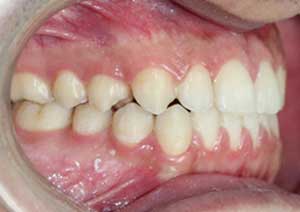

Le cross-bite antérieur (ou articulé croisé antérieur) est une anomalie d’occlusion dans laquelle une ou plusieurs dents du maxillaire se retrouvent en arrière des dents mandibulaires, alors qu’elles devraient être en avant.

Traitement : Dans ce cas, nous avons eu recours à la mise en place de cales postérieures en résine bleue au niveau des premières molaires maxillaires, Elles ont permis de séparer temporairement les mâchoires afin de laisser les dents du haut se replacer correctement devant celles du bas, corrigeant ainsi le cross-bite antérieur.

Avant